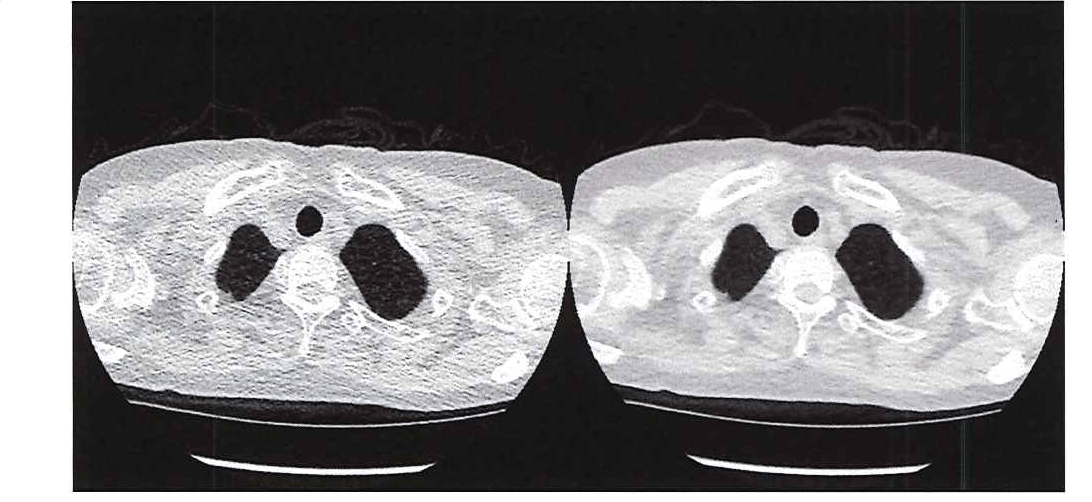

의학자들은 의사들이 필요로 하는 이미지 선명도를 제공하는 동시에 방사선 노출을 제한할 방법을 찾고 있습니다. 한 가지 유망한 방법은 초저선량 CT를 사용하는 것으로, 흉부 이미지의 평균 유효 선량이 약 0.13mSv입니다. [1] 초저선량 CT 스캔의 주요 단점은 해상도가 상대적으로 낮고 노이즈가 크다는 것입니다. 이로 인해 의사가 장기, 지방, 간질 조직을 확인하기 어려울 수 있습니다(그림 1).

그림 1. 초저선량 CT(왼쪽)와 기존 CT(오른쪽)의 이미지 품질 비교.